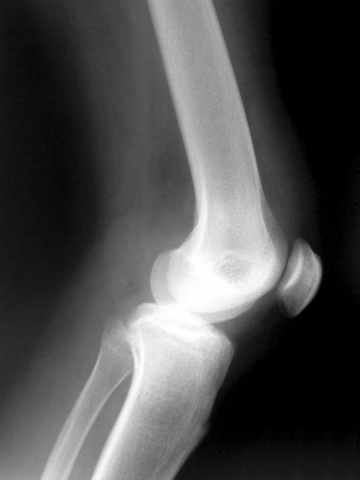

RZS – Reumatoidalne Zapalenie Stawów, w dawniejszym nazewnictwie występuje pod nazwą GPP – Gościec Przewlekle Postępujący. Jest to schorzenie stawów kończyn górnych i dolnych, a także może występować we wszystkich stawach kręgosłupa, z Czytaj dalej